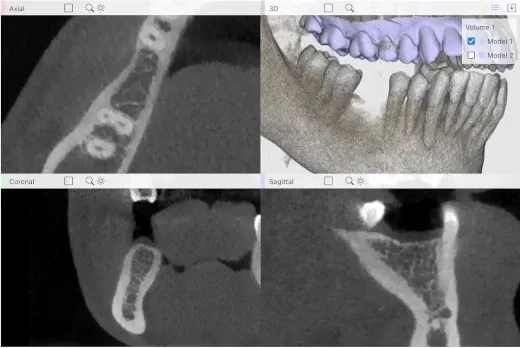

A free lightweight web-based 3D viewer for visualizing CBCT volumes and STL models.